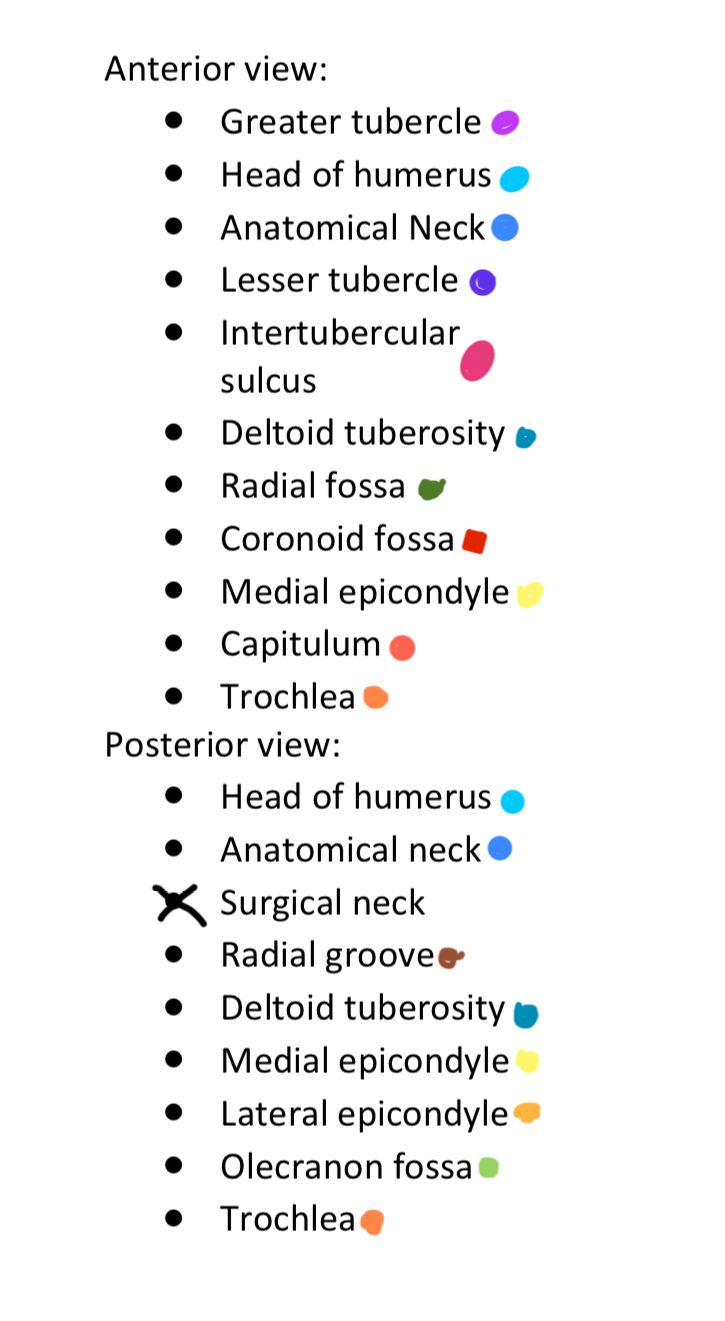

Anterior & Posterior Views of the Humerus

14 Terms

1

New cards

Light Purple

Greater Tubercle

2

New cards

Light Blue

Head of Humerus

3

New cards

Dark Blue

Anatomical Neck

4

New cards

Dark Purple

Lesser Tubercle

5

New cards

Pink

Intertubercular Sulcus

6

New cards

Cyan

Deltoid Tuberosity

7

New cards

Dark Green

Radial Fossa

8

New cards

Red

Coronoid Fossa

9

New cards

Yellow

Medial Epicondyle

10

New cards

Salmon

Capitulum

11

New cards

Dark Orange

Torchlea

12

New cards

Brown

Radial Groove

13

New cards

Light Orange

Lateral Epicondyle

14

New cards

Light Green

Olecranon Fossa